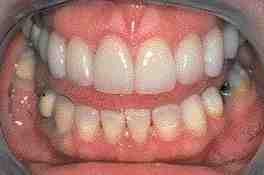

Abstract: The use of new metal-free esthetic restorative systems and new restorative techniques have become abundant in the last decade. These restorative techniques and systems enhance the ability to provide the majority of patients with esthetic, functional, and long-lasting crowns. However, one must take care while treating bruxing patients, especially if a full-mouth fixed rehabilitation is required. The new restorative systems and techniques might not provide adequate strength to withstand the bruxer’s parafunctional activity and might not insure the longevity of the restoration. Therefore, with prudent diagnosis and treatment planning, both of which are paramount in order to prevent the failure of the treatment, the restorative dentist must rise to the challenge of treating the bruxer. He/she should consider the use of metal-ceramic restorations with porcelain labial margins on anterior teeth and with 360 degrees metal margins on posterior teeth. Thus, providing these patients with a functional as well as an esthetic rehabilitation with adequate longevity. To illustrate this approach, this article will demonstrate through the following case report, the full-mouth fixed rehabilitation of the bruxing patient.